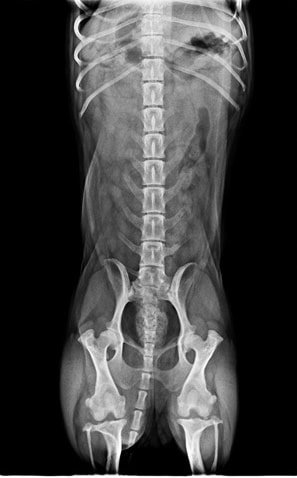

3.X光片

左邊膝蓋是鬆的,但走路看起來很好

沒有跑一跑突然掰咖,舉例來說紅貴賓容跑一跑跛腳,膝蓋會甩一下

膝關節異位這類的情況,但如果不影響日常生活就不需要手術的

左腳的膝關節有點偏移

tila是臘腸犬,可以補充關節軟骨保護劑,當作保養

有稍微擠迫一點點,但基本神經學檢查反應~腳腳的肌肉都非常好

髖關節的部分和以前沒差多少,以100分來說算85分

以臘腸品種這年紀來說算漂亮的,即早保養最好、神經傳導目前看也都好

髖關節右腳比左腳漂亮一點點 ((很愛用漂亮形容

骨骨頭左邊沒有那麼圓潤、股骨頸沒有過度的增粗

胸腰椎,每個椎體間隔都還漂亮、不會過度狹窄

胸腔、腹腔、心肺都很乾淨!漂亮!

血管很明顯

胸腔也都乾淨、無擴張,心臟大小跟以前差不多

心臟看起來很大,但臘腸狗的比例算是標準的

不用進階心臟照超音波